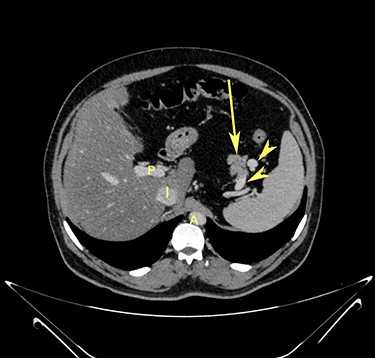

Transverse section image of a contrast-enhanced CT scan of the abdomen at the level 3–3 (Fig. 1), showing a solitary cyst (arrow) with a non-enhancing wall separate from the intestines.